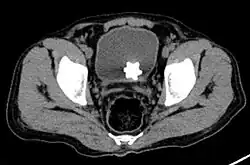

Jackstone calculus

Jackstone calculi are rare bladder stones that have an appearance resembling toy jacks. They are almost always composed of calcium oxalate dihydrate and consist of a dense central core and radiating spicules. They are typically light brown with dark patches and are usually formed in the urinary bladder and rarely in the upper urinary tract. Their appearance on plain radiographs and computed tomography in human patients is usually easily recognizable. Jackstones often must be removed via cystolithotomy.[10]